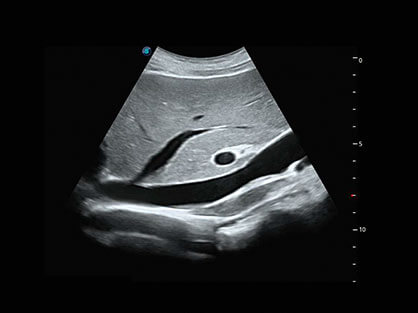

宽频带腹部凸阵探头和腹部容积探头、大角度腔内探头和腔内容积探头、独特的生殖专用曲柄探头,为妇产应用提供全面诊疗方案。

卵泡结构的自动识别和测量,可显示多组测量数据。

大角度腔内容积探头,可完整包络子宫及盆底结构,充分展示组织结构毗邻关系。